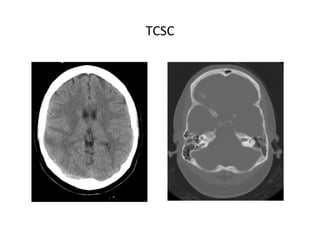

TCSC

• TC SIN CONTRASTE IV

Para descartar patologías con síntomas similares (infartos

arteriales, tumores o procesos infecciosos), aunque en un

25% de las TVC podemos no encontrar hallazgos

significativos.

SIGNOS DIRECTOS

Hiperdensidad homogénea durante las 2 primeras semanas:

- Signo de la cuerda densa: por trombosis aguda de venas

corticales.

- Seno lateral denso

- Vena yugular densa

- Triángulo denso (SSS)